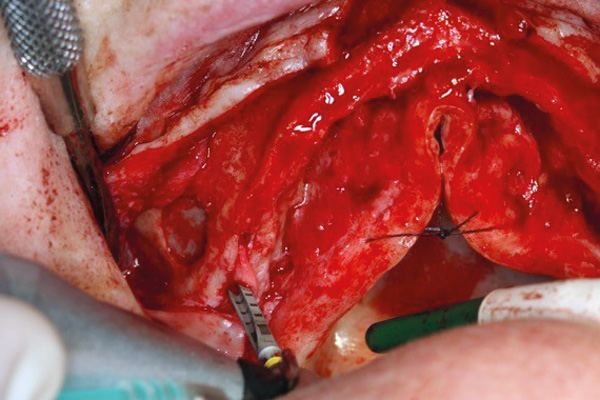

02/11 - View of the maxilla after elevating the flap